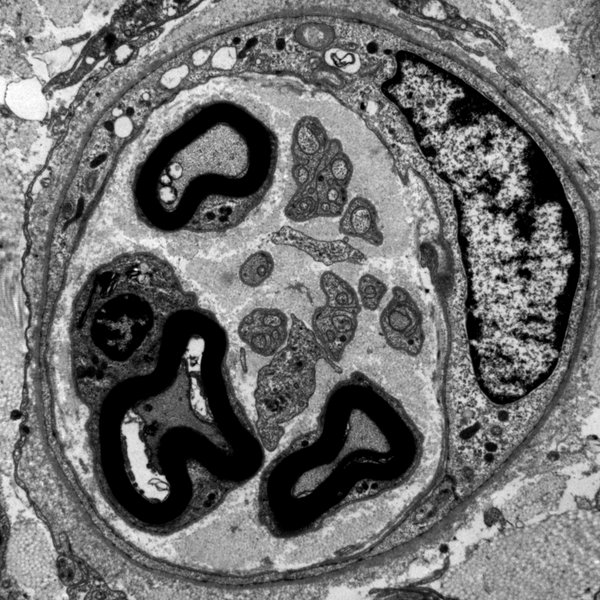

Die Methoden, die von unserer Arbeitsgruppe angewandt und gelehrt werden, spannen einen Bogen von der Licht- über die Elektronenmikroskopie bis hin zur Molekularbiologie. Neben den qualitativ, beschreibenden Methoden ist auch die quantitative Morphologie vertreten.